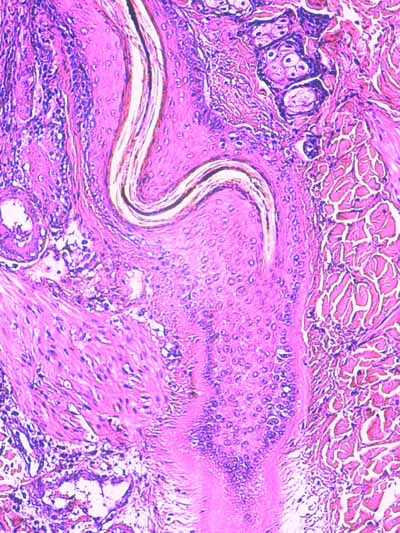

Biopsies cutanées

Sur l’une des biopsies, l’épiderme et les structures annexielles sont nécrosées ainsi que de larges plages de fibres de collagène dans le derme profond (Fig6). Dans le derme périannexiel, on observe une discrète hypercellularité diffuse sous la forme de cellules pycnotiques (Fig2,3,13,14). En profondeur, dans l’hypoderme, on observe une dilacération des septa conjonctifs interlobulaires et des adipocytes par un matériel sérofibrineux, parsemé d’une poussière nucléaire entourant parfois des structures vasculaires, artériolaires et veineuses, de moyen calibre dont la lumière est occupée par un thrombi fibrineux et dont les cellules endothéliales apparaissent vacuolisées (Fig7,8,9). Sur les autres biopsies, l’épiderme montre des lésions de dégénérescence réticulaire (Fig3,4,5). Cet aspect est associé à un décollement épidermique multifocal(Fig2,3). Le derme superficiel est œdémateux (Fig3,4,5). Au sein des unités annexielles, on observe plusieurs follicules pileux dont la gaine épithéliale folliculaire externe, est plissée sur toute sa longueur. La tige pilaire présente dans le canal pilaire est elle-même circonvolutée, fracturée, la cuticule effritée (Fig2,10,11,12) . Le cycle folliculaire est normal, la phase anagène prédomine. Autour des structures annexielles, on observe de petits foyers de taille variable, nécrotiques, avec une poussière cellulaire et probablement un matériel fibrinoïde (Fig13,15). On perçoit encore la silhouette de certaines structures vasculaires dont la lumière semble obstruée de thrombi. On en retrouve, dans les septa conjonctifs interalvéolaires, des lobules adipeux. A noter, que sur l’une des biopsies, se trouvent incluses dans le tissu adipeux, des tiges pilaires tortueuses. Dans plusieurs territoires dermiques nécrotiques, on observe, au fort grossissement à l’objectif à immersion, des silhouettes vasculaires tapissées de reliquats de cellules endothéliales, au cytoplasme vacuolisé avec chromatolyse nucléaire. En périphérie, les fibres de collagène prennent un aspect coagulé, basophile. Elles montrent une multitude d’éléments bacillaires associés à des dépôts acidophiles, probablement fibrinoïdes (Fig16).

Photo 2 (Hémalun Eosine X 40) : biopsie réalisée en marge d’un ulcère.

L’épiderme, fragilisé, se détache artéfactuellement et se désolidarise du derme superficiel.

Le derme montre une plage cellulaire dense qui s’étend du derme superficiel jusqu’au derme profond.

En contact avec cette plage, se trouve un follicule pileux dont la tige pilaire est fragmentée

et circonvolutée dans son fourreau épithélial.

Légendes de la Photo 2 :

- Pointe de flèche orange : ulcère

- Ovale jaune : plage cellulaire inflammatoire s’étendant du derme superficiel au derme profond

- Flèche turquoise : follicule pileux dont la tige pilaire est fragmentée et circonvolutée dans son fourreau épithélial

- Flèches jaunes : épiderme fragilisé qui se détache du derme

- Double flèche orange : épaisseur épidermique

- Double flèche verte : épaisseur dermique

- Double flèche bleue : épaisseur hypodermique